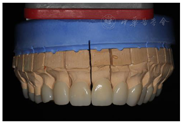

架

架临时修复体患者戴用无不适,上颌牙制作永久修复体,戴牙(图32,图33)。同样,对下颌牙进行牙体预备,取模,制作永久修复体,戴牙(图34,图35,图36,图37,图38,图39)。